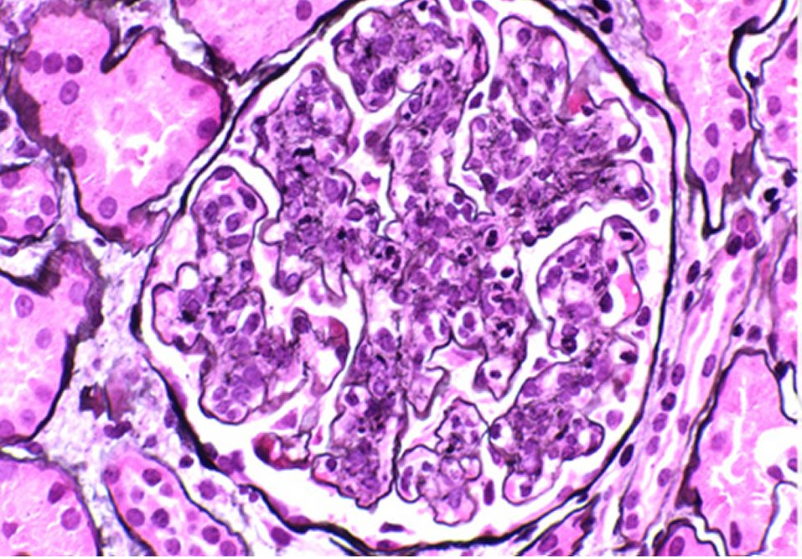

La asignatura de Histología para Patólogos es de carácter teórico-practico permite al estudiante un conocimiento profundo sobre los aspectos estructurales y funcionales de los tejidos y órganos a nivel microscópico. Esta materia es fundamental en la formación de especialistas en Anatomía Patológica, ya que les permite correlacionar los hallazgos microscópicos con las manifestaciones clínicas, lo que es clave en el diagnóstico y manejo de enfermedades.Tiene como objetivos Proporcionar a los estudiantes los conocimientos avanzados sobre la estructura histológica normal de los diferentes tejidos y órganos del cuerpo. Desarrollar habilidades en la interpretación de preparaciones histológicas, con especial énfasis en la correlación clínico-patológica. Fomentar el pensamiento crítico en la interpretación de alteraciones histológicas, relacionándolas con procesos patológicos.